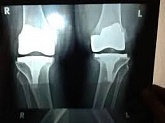

Еndoprosthesis of knee joint

In the late stages of arthrosis of the knee joint, accompanied by a pronounced restriction of the volume of movements, constant intense pain, deformity of the limb, the only way to recover is to replace the affected joint with an artificial joint - arthroplasty.

This method allows you to return the correct form of the limb, the full volume of movements in the joint, relieve the constant pain and crunch during movements and, as a result, significantly improve the patient's quality of life.

Below are presented X-ray photographs and photographs, illustrating the amount of motion in the affected joint before and after surgery.